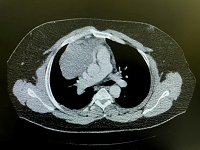

Spontaneous Regression of a Thymoma with Mild Pleural Effusion: A Case Report

Abdulaziz Alnassar

International Journal of Innovative Research in Medical Science·January 13, 2023